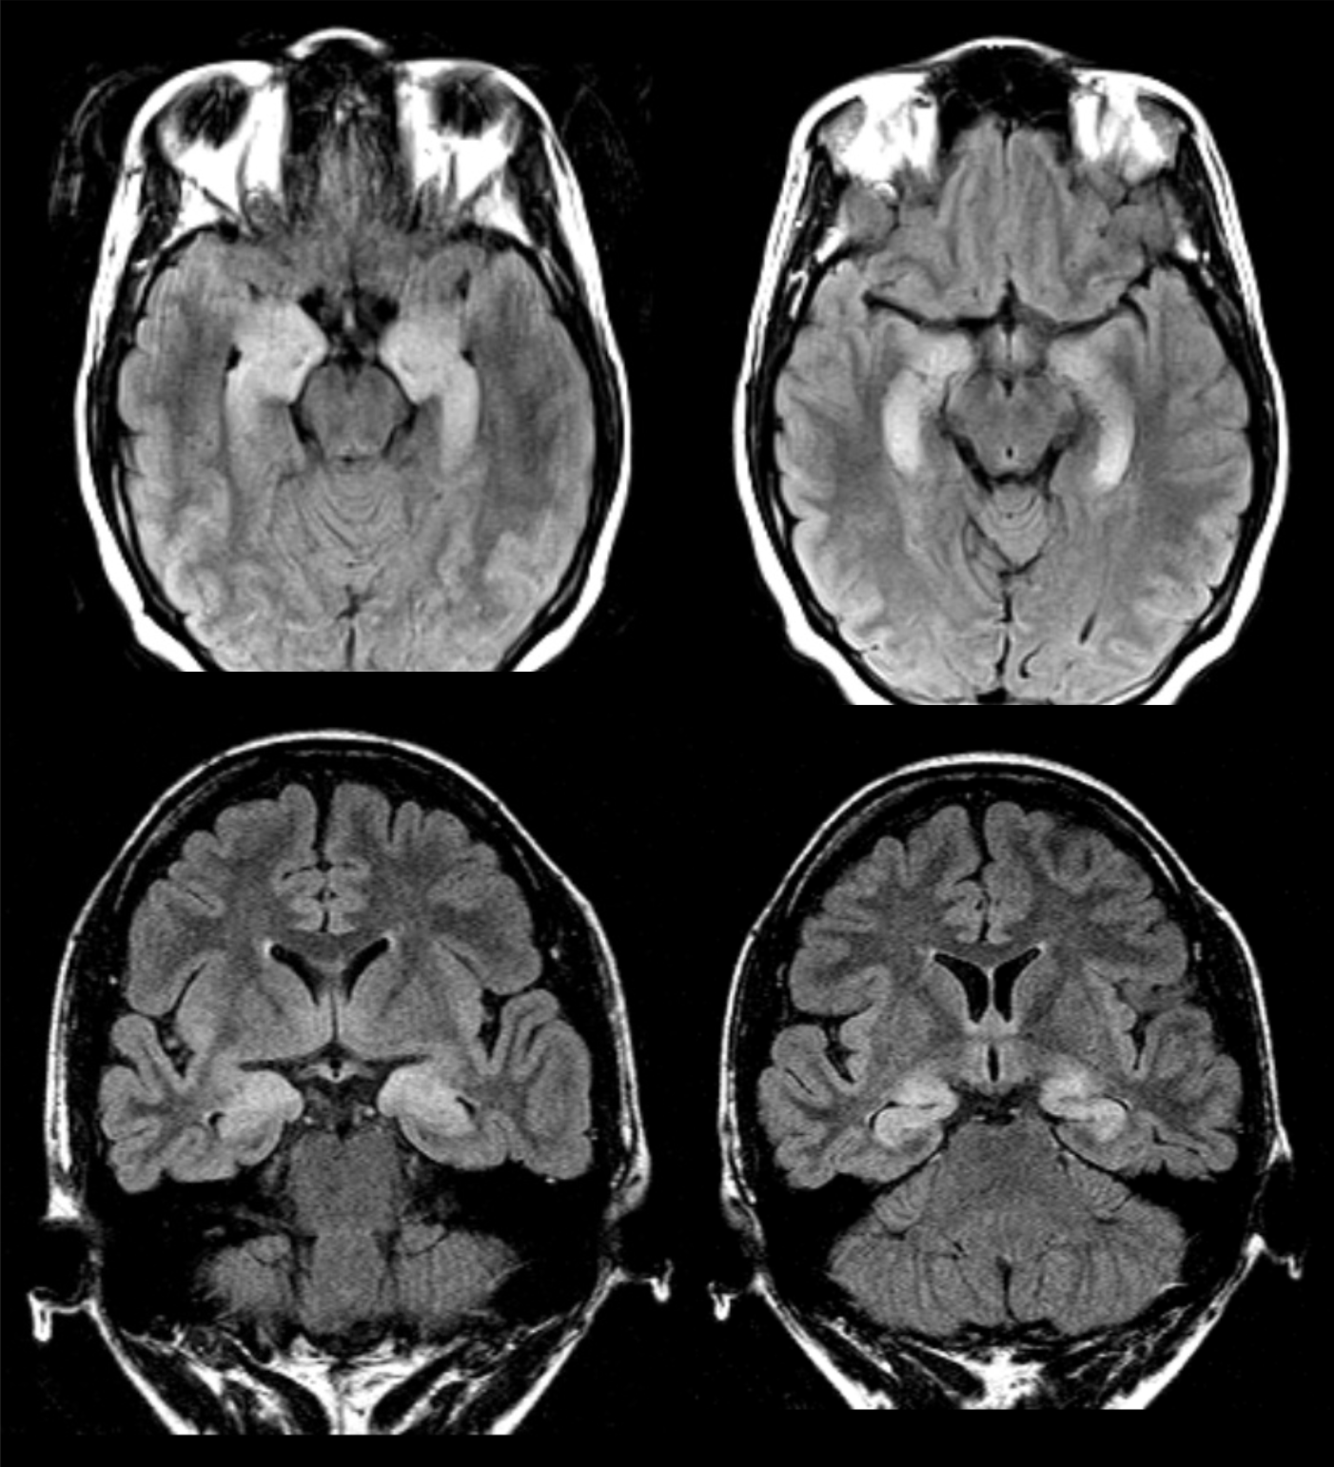

48 y/o M admitted for ETOH withdrawal, became encephalopathic and parkinsonized in hospital.

Central pontine and extrapontine myelinolysis